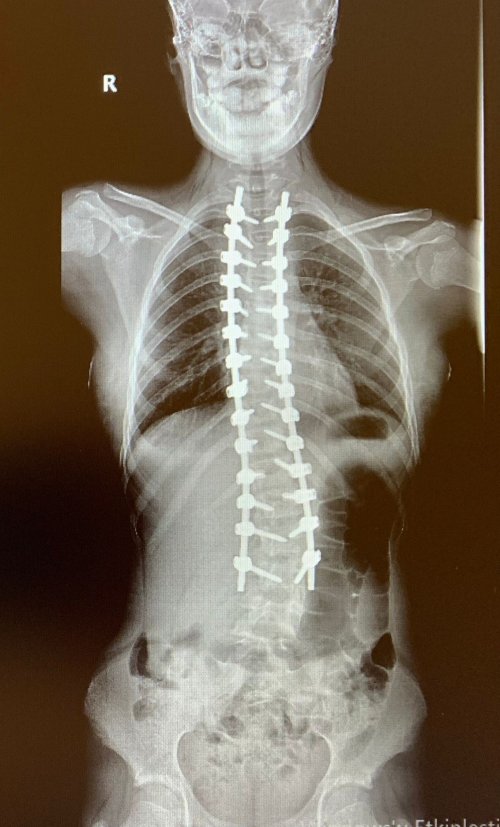

Aydın’da yaşayan 12 yaşındaki Gökçe Uçar’ın sol omzunda beliren çıkıntı ve yaşadığı ağrılar sebebiyle ailesi, kızlarını doktora götürdü. Yapılan testlerde, küçük kızın ergenliğe girmesi ve bir anda hızlı boy atmasıyla birlikte omurgasında S biçiminde eğrilik oluştuğu ortaya çıktı. Füzyon denilen dondurma yöntemiyle ameliyat edilen Gökçe sağlığına kavuşurken, ameliyatı gerçekleştiren Ortopedi ve Travmatoloji Uzmanı Doç. Dr. Mutlu Çobanoğlu, skolyozun toplumun yüzde 2’lik bir kısmında görüldüğünü belirterek, çocuklarının sırtında çıkıklık, omuzda düşüklük ya da belinde şişlik gibi belirtiler gören ailelerin mutlaka bir uzmana başvurmaları gerektiğini ifade etti.

6'ıncı sınıf öğrencisi 12 yaşındaki Gökçe Uçar da zaman zaman sırtında ağrı yaşıyordu. Dönem dönem ağrıları şiddetlenen küçük kızın sırtında bir eğrilik olduğunu ilk ablası fark etti. Babası Aytaç Uçar ise, kızının yaz günü çok fazla bisiklet kullandığını, çoğunlukla da tek elle kullanmasından kaynaklı bir durum olabileceğini düşünse de yapılan tetkiklerde durum farklı çıktı. Gökçe’nin omurgası oldukça eğriydi. Skolyoz derecesi düşük olan kişilerde daha çok egzersiz ve korse ile takibinin yapıldığını belirten Medicana International İzmir Hastanesi Ortopedi ve Travmatoloji Uzmanı Doç. Dr. Mutlu Çobanoğlu, Gökçe’nin eğrilik derecesinin 60 derece olması nedeniyle ameliyat edilmesine karar verdi.

Gökçe’nin ameliyatını gerçekleştiren Ortopedi ve Travmatoloji Uzmanı Doç. Dr. Mutlu Çobanoğlu, hastanın yaşına göre farklı ameliyat teknikleri olduğunu ancak 10 yaşından önce omurgalara kaynaştırma ve dondurma da denilen füzyon ameliyatı yapmak istemediklerini belirterek, “Eğer hastalık erken dönemdeyse büyüme dostu yöntemleri tercih ederiz ancak artık büyüme potansiyeli azalmış ve yüksek skolyoz derecesi olan kişilerde füzyon tekniği evrensel bir yöntem. Biz de Gökçe’de bunu tercih ettik. Eğriliğin olduğu bölgedeki kemikleri kaynaştırıp tek kemik haline getiriyoruz. Kemik aşıları ile destekleyerek kemiklerin birbirine kaynamasını sağlıyoruz” diye konuştu.